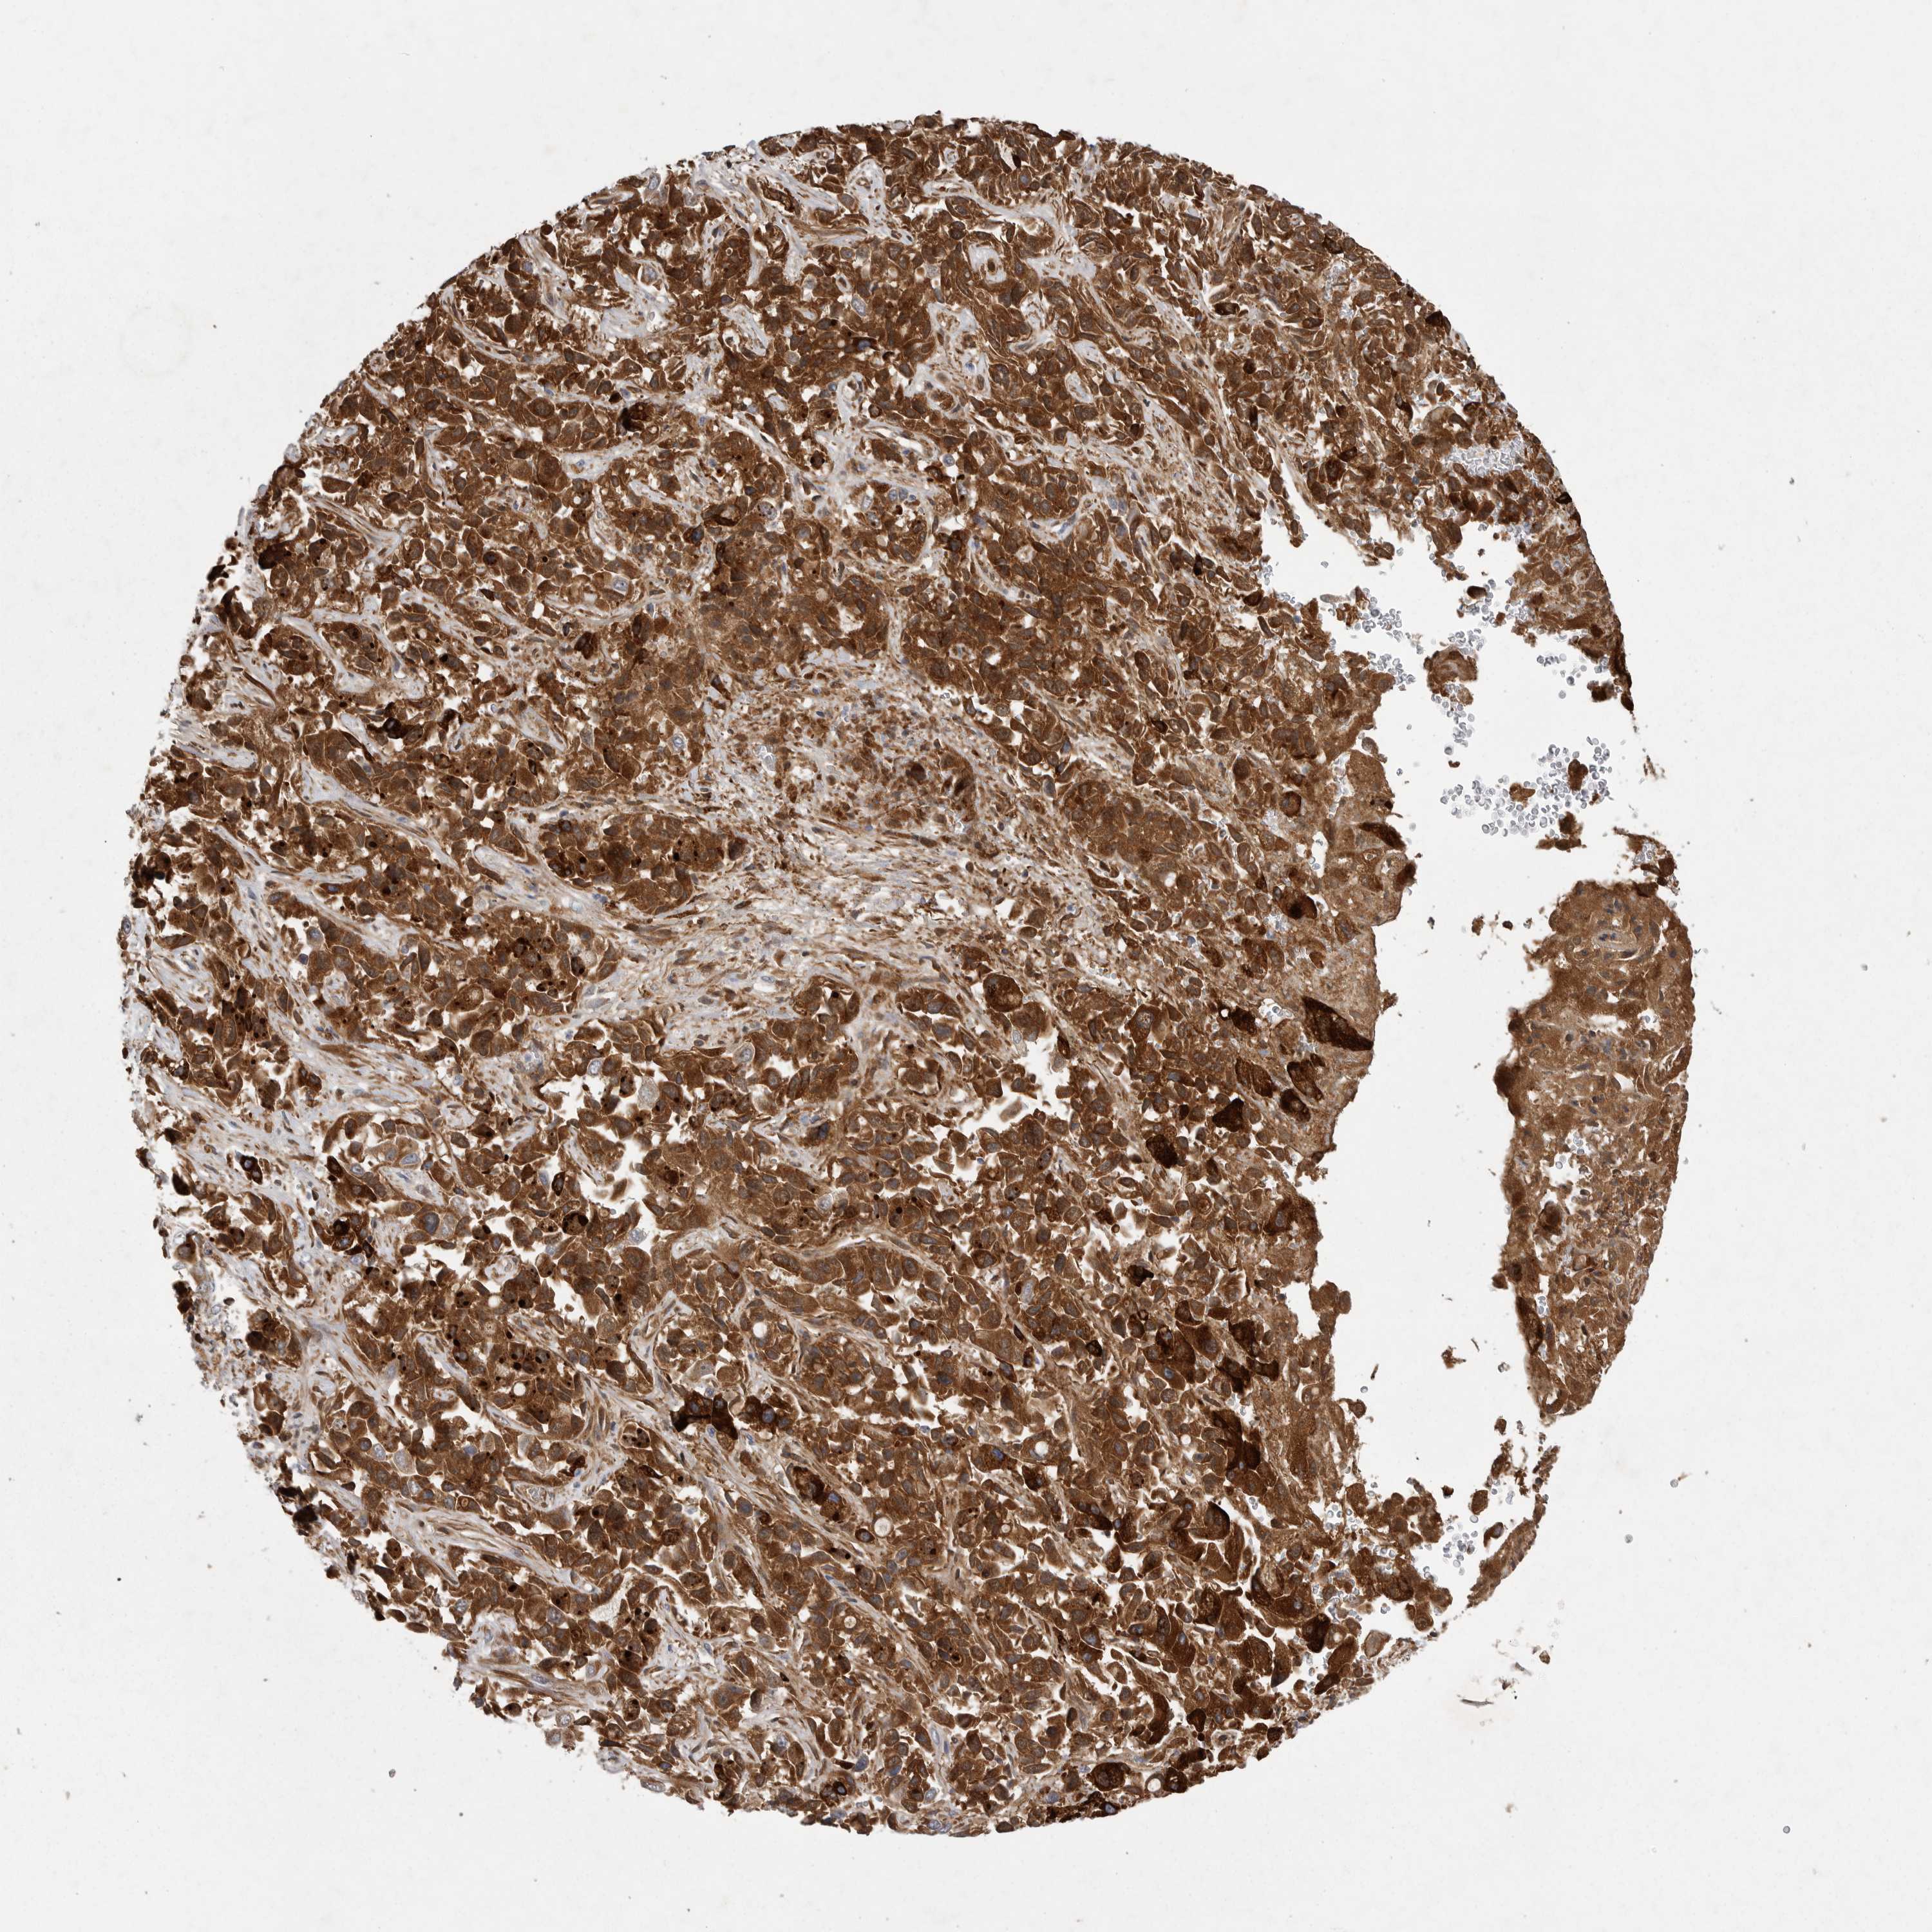

LIVER CANCER - Protein expressioni

A mouse-over function shows sample information and annotation data. Click on an image to view it in a full screen mode. Samples can be filtered based on level of antibody staining by selecting one or several of the following categories: high, medium, low and not detected. The assay and annotation is described here.

Note that samples used for immunohistochemistry by the Human Protein Atlas do not correspond to samples in the TCGA dataset.

Antibody stainingi

Antibody staining in the annotated cell types in the current human tissue is reported as not detected, low, medium, or high, based on conventional immunohistochemistry profiling in selected tissues. This score is based on the combination of the staining intensity and fraction of stained cells.

Each image is clickable and will lead to virtual microscopy that enables deeper exploration of all samples and also displays staining intensity scores, fraction scores and subcellular localization as well as patient and tissue information for each sample.

Antibody HPA027367

Antibody HPA027396

Antibody CAB005036

Staining

High

Medium

Low

Not detected

Intensity

Strong

Moderate

Weak

Negative

Quantity

>75%

75%-25%

<25%

None

Location

Nuclear

Cytoplasmic/membranous

Cytoplasmic/membranous,nuclear

Cholangiocarcinoma

Carcinoma, Hepatocellular, NOS